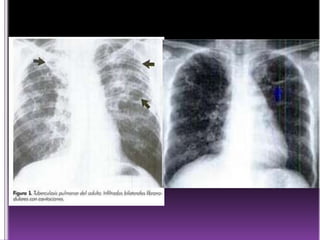

 Exclusivo de las cavernas de tuberculosis

(espeluncas)

 Cavitación: creación de un espacio en el interior

de una lesión, de contenido necrótico, detritus,

sangre o gas.

 Inicia lesión alveolar expandiéndose y

lesionado tejido circundante.

 Periferia, supraclaviculares

 Hiliares

 Basal

 Según el tiempo de proceso exudativocaseificacion

 Distinto tamaño

 Migas pan o panal de abejas